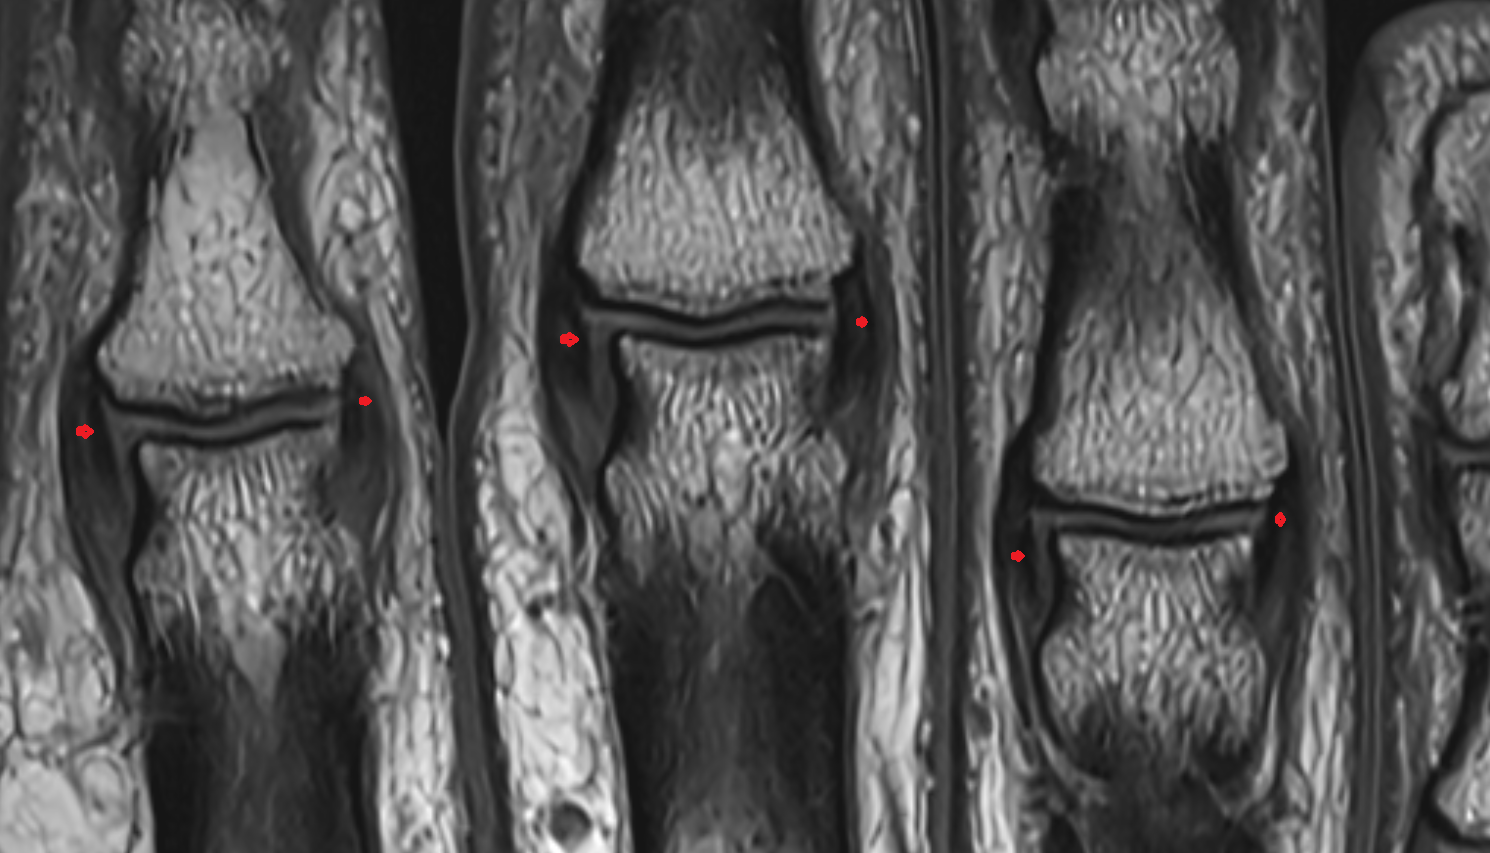

- Medial meniscus

- Lateral meniscus

- Anterior horn of medial meniscus

- Posterior horn of medial meniscus

- Body of medial meniscus

- Anterior horn of lateral meniscus

- Posterior horn of lateral meniscus

- Body of lateral meniscus